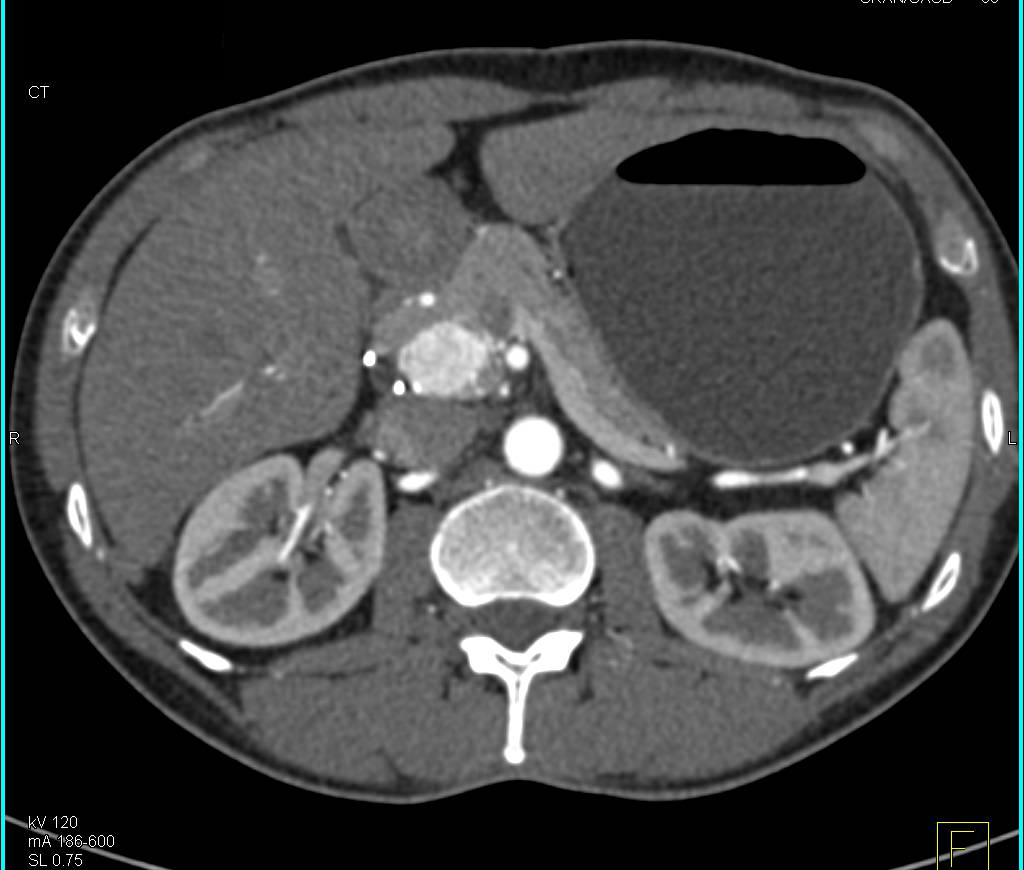

Multiple Intraductal Papillary Mucinous Neoplasms (IPMNs) with High Grade Dysplasia